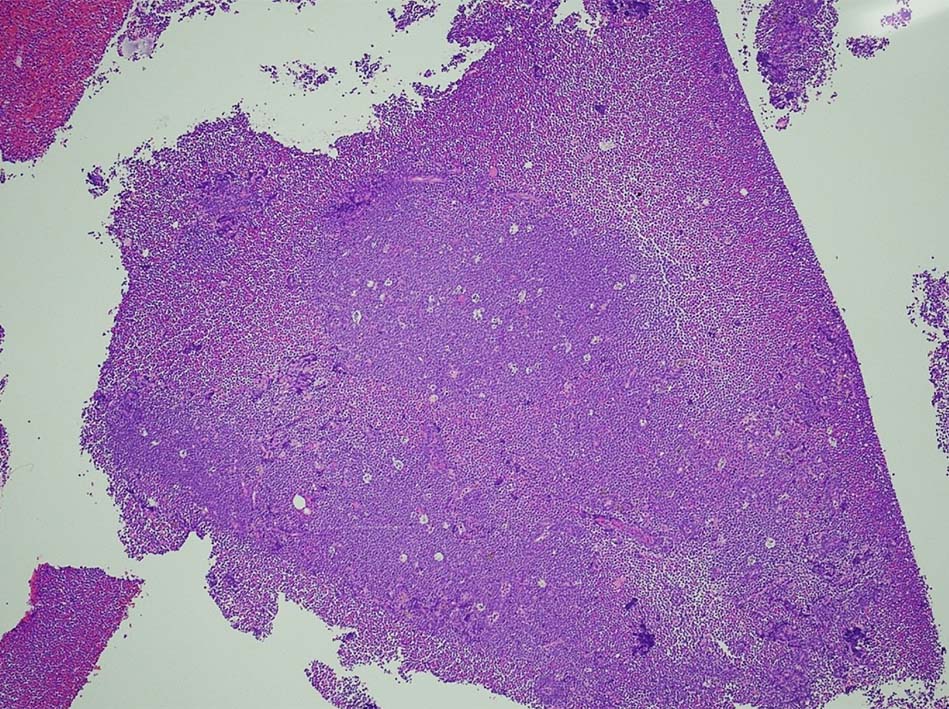

T-lymphoblastic leukaemia/ lymphoma

Tリンパ芽球性白血病/リンパ腫、NOS( WHO5th classification*1)

慣例では、末梢血および骨髄が主要病変部位である場合は白血病(T-ALL), リンパ節、胸腺またはその他の結節外部位が主要病変部位である場合はリンパ腫(T-LBL)という用語を使用する。

Tリンパ芽球性白血病とTリンパ芽球性リンパ腫の区別は、臨床像および骨髄浸潤の程度に基づいて行われる。白血病は、末梢血および/または骨髄に著明な浸潤を認める疾患(通常、骨髄芽球25%以上とみなされる)を指すのに対し、リンパ腫は、胸腺、リンパ節または節外部位への浸潤を含む、組織ベースの腫瘤性病変を指し、末梢血または骨髄への浸潤はないか、あってもごくわずかである*2。 末梢血/骨髄の浸潤と腫瘤性病変の両方がある場合は、有意な区別はない。一般に、両者には生物学的および臨床的に大きな重複があり、WHOの分類スキーム(WHO4th rev Ed 2017)によれば、臨床像の異なる同一疾患とみなされる。

T-ALL/LBL 縦隔腫瘍, 胸水貯留症例

70歳男性 KNS

右肺上葉から前縦隔に90mm大の腫瘤あり. 右胸水貯留を伴う. 右主気管支よりEBUS-TBNAをおこなう.